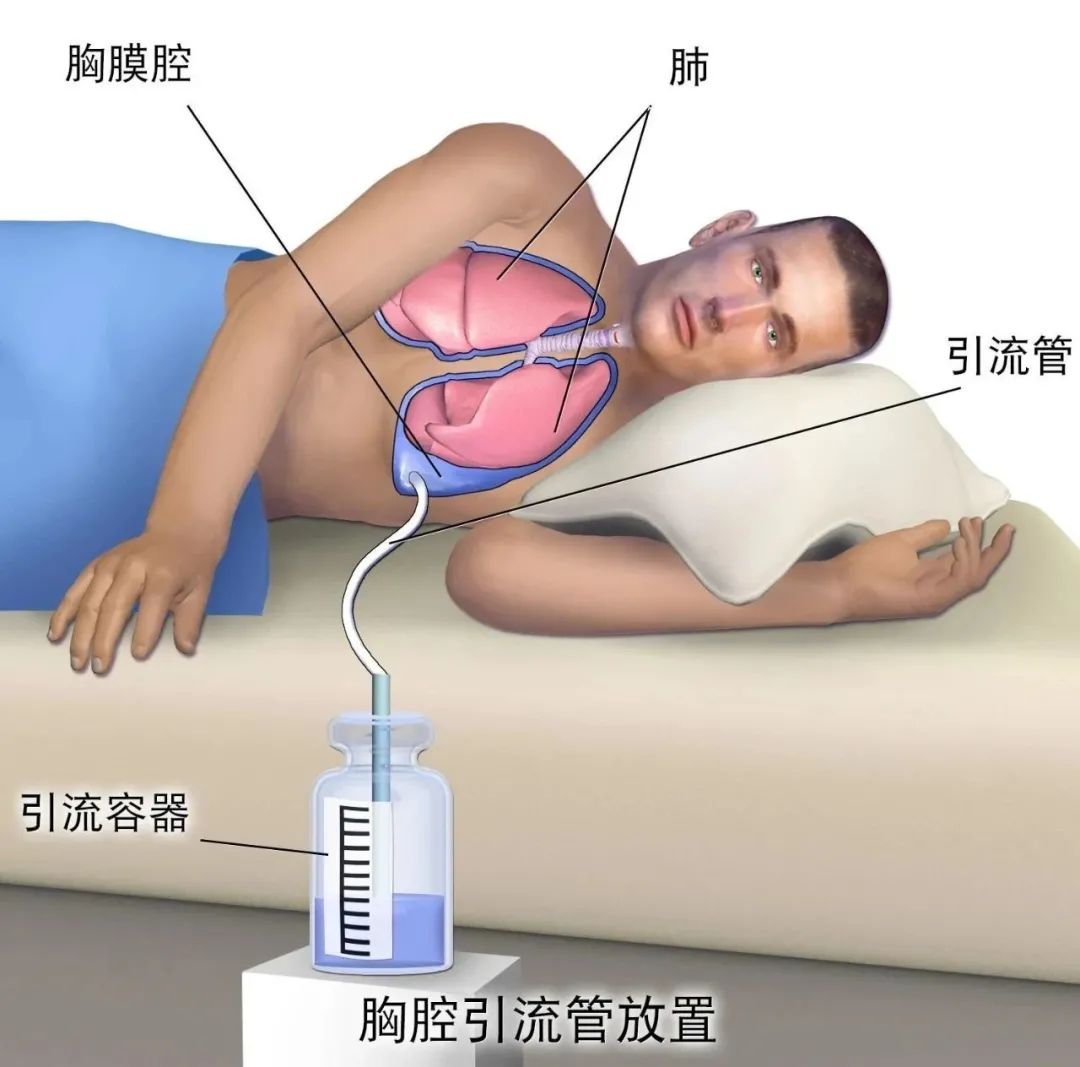

一文说全:肺癌患者如何控制胸水!